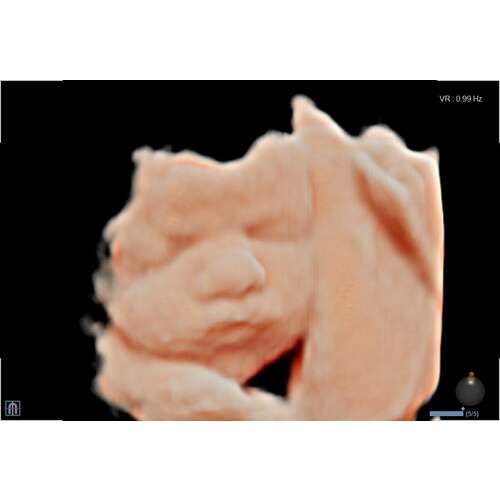

Ik heb de echo met 27 weken laten doen.. Ook placenta aan de voorkant en de kleine jongen vond het heeeeeerlijk om er steeds met z’n gezichtje in te zitten🫣

Ik allerlei manoeuvres uithalen dat hij toch wat ging draaien, maar helaas! Eenmaal er iets af deed hij z’n handjes voor z’n gezicht 😅

Uiteindelijk hebben we toch nog wel een goeie echo kunnen krijgen!

We hoefden niet alles te betalen, omdat het niet helemaal goed gelukt was.